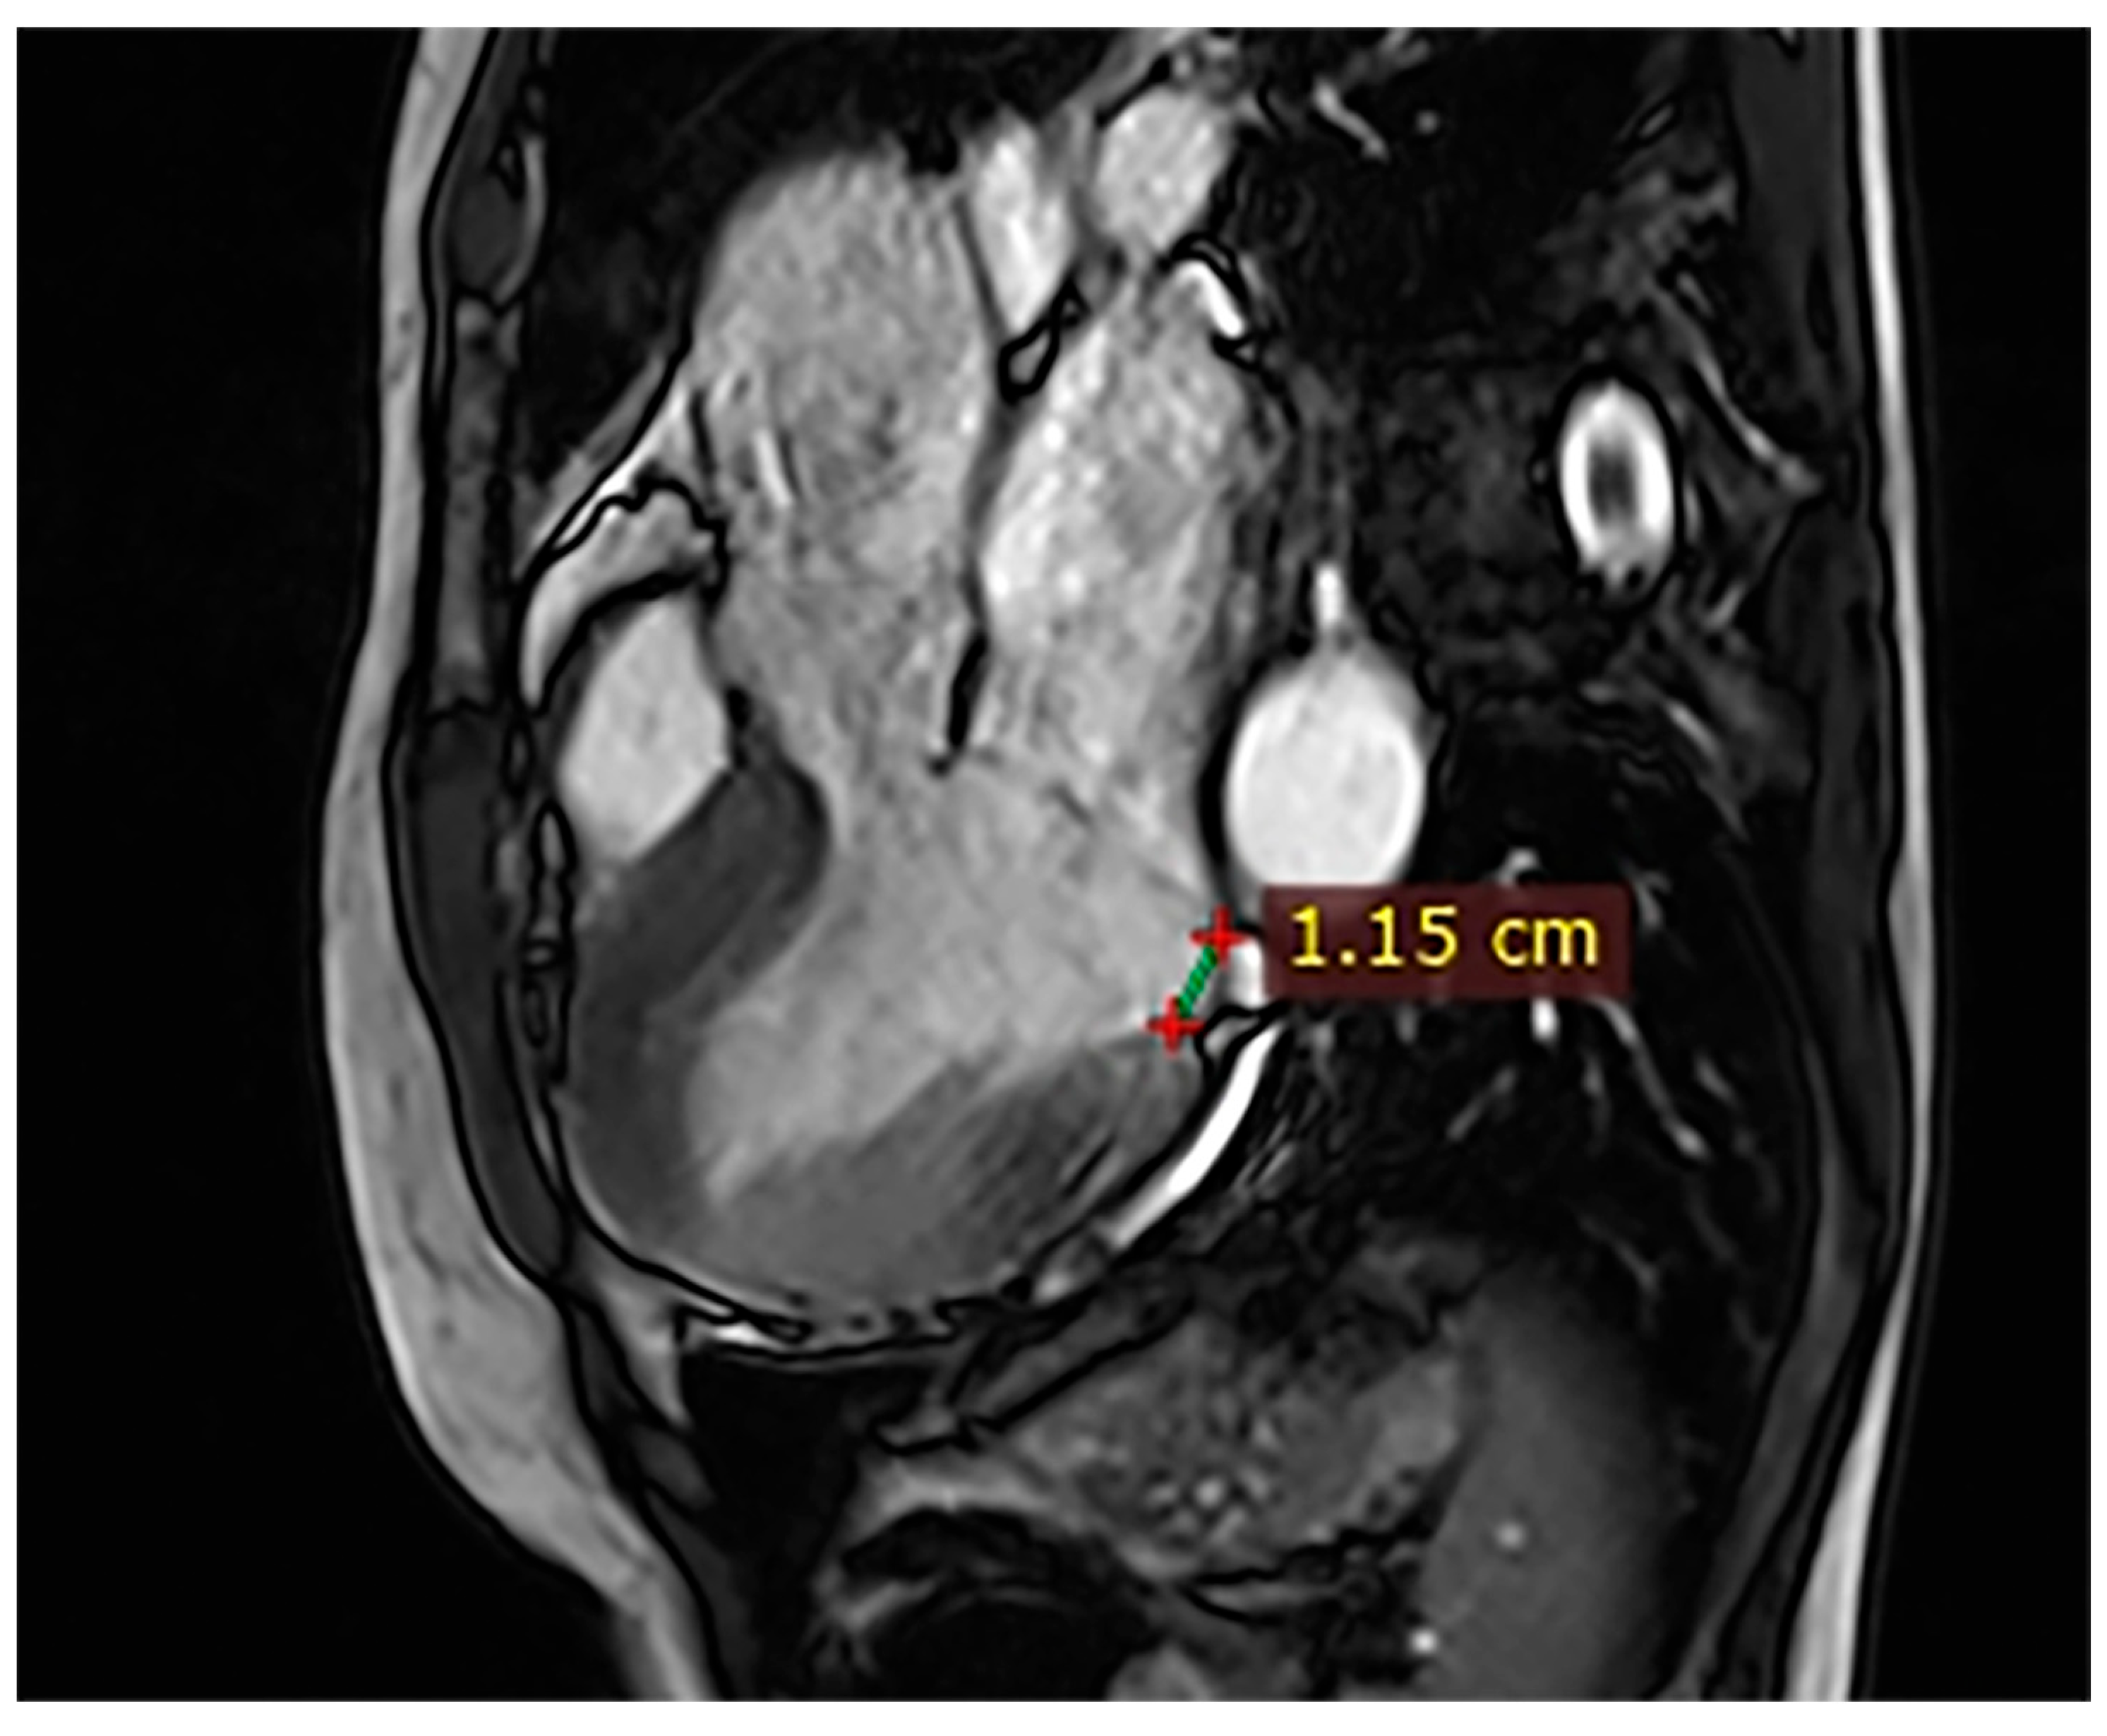

| 1 | Female, 61 years old | Syncope | 11 | MVP, mitral regurgitation | Lateral | Holter: atrial tachycardia and ventricular ectopy; cardiology follow-up planned for possible mitral valve repair |

| 2 | Male, 52 years old | Syncope and atypical chest pain | 10 | - | Lateral | History of ventricular arrhythmias; cardiology follow-up and Holter monitoring recommended |

| 3 | Female, 74 years old | Extrasystole | 3 | - | No LGE | No LGE; patient reassured and scheduled for periodic clinical follow-up |

| 4 | Male, 34 years old | Extrasystole in Marfan syndrome | 15 | MVP, valvular regurgitation | No LGE | Marfan syndrome; MVP with regurgitation; regular cardiology follow-up advised. |

| 5 | Male, 63 years old | Heart failure | 2,5 | MVP, valvular regurgitation | No LGE | Reduced LVEF (47%) with left atrial dilatation; heart failure therapy optimized; follow-up planned. |

| 6 | Male, 68 years old | Palpitations | 5 | - | Lateral | LGE in basal lateral wall; electrophysiological evaluation and ECG monitoring recommended. |

| 7 | Female, 53 years old | Extrasystole and syncope | 15 | MVP, valvular regurgitation | Basal-lateral | Extensive MAD with MVP and LGE; increased arrhythmic risk; antiarrhythmic therapy considered. |

| 8 | Female, 63 years old | Aortic and mitral regurgitation | 11 | Aortic and mitral regurgitation | Lateral | Aorto-mitral regurgitation with septal hypokinesia; mitral valve repair performed; heart failure therapy started. |

| 9 | Male, 45 years old | Palpitations and vertigo | 10 | - | Lateral | Basal lateral LGE; regular clinical and ECG follow-up recommended |